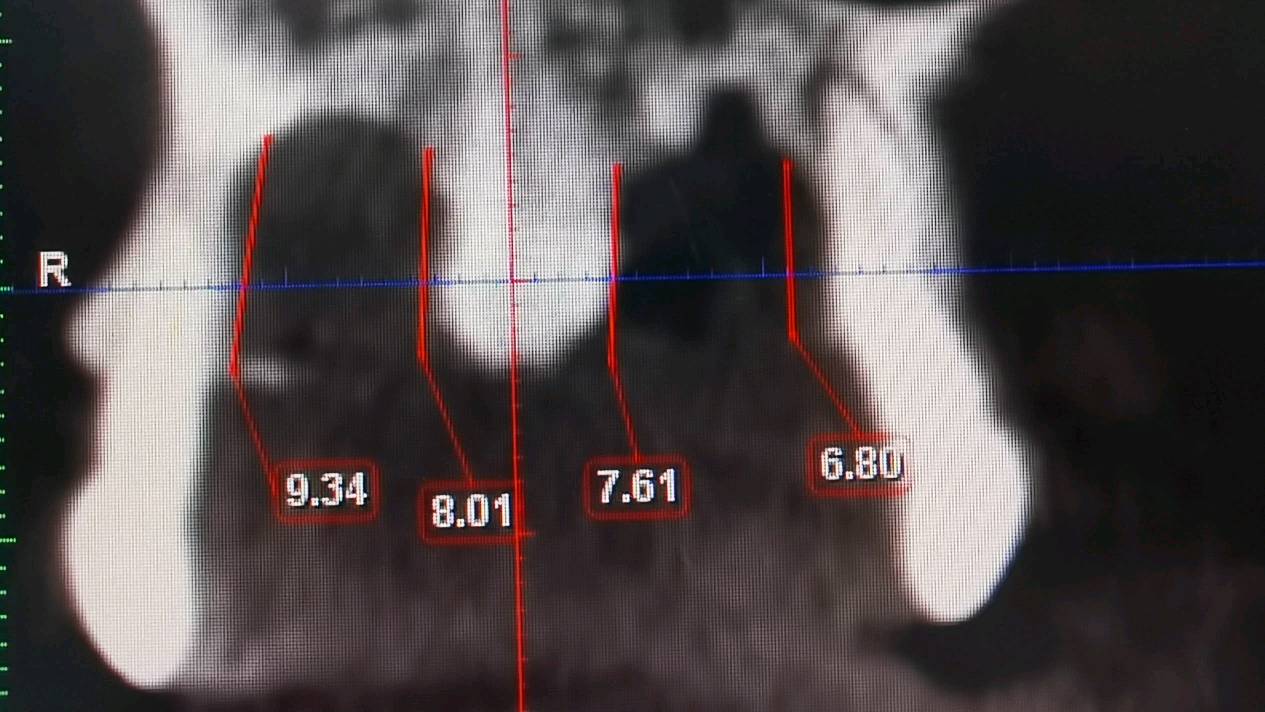

a.术前准备拍摄颌面部 CBCT ,评估骨质骨量,设计种植体植入的位置、轴向、直径和长度。

c、即刻植入根据拔牙窝的位置方向和颌骨的解剖形态,将钻头方向贴着腭侧骨板,采用逐级备洞的方法制备种植窝,植入适当长度和直径的种植体。即刻修复如种植体初期稳定性≥35N/ cm ,可行即刻修复。术中行数字化无痛印模,送工厂行高精度义齿制作,1周内复诊,行义齿戴入,所有即刻修复体均调整至正中、前伸和侧方咬合均无接触。根据种植愈合情况,即刻修复3-6个月后再行永久修复

3.5倍显微镜下拔牙,刮囊肿,植入ITI 种植体。